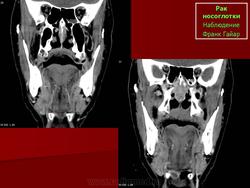

ЛОР. Онк. Рак носоглотки. +

Рак носоглотки